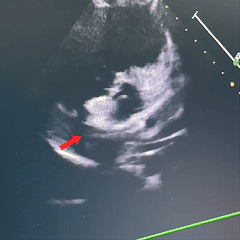

二维超声心动图:

沿房间隔可见封堵装置,沿其周围未测及残余分流。

房室腔正常大小,房室瓣开放活动可。

多普勒超声心动图:各瓣膜血流速度正常。

超声提示:ASD封堵术后,无残余分流。